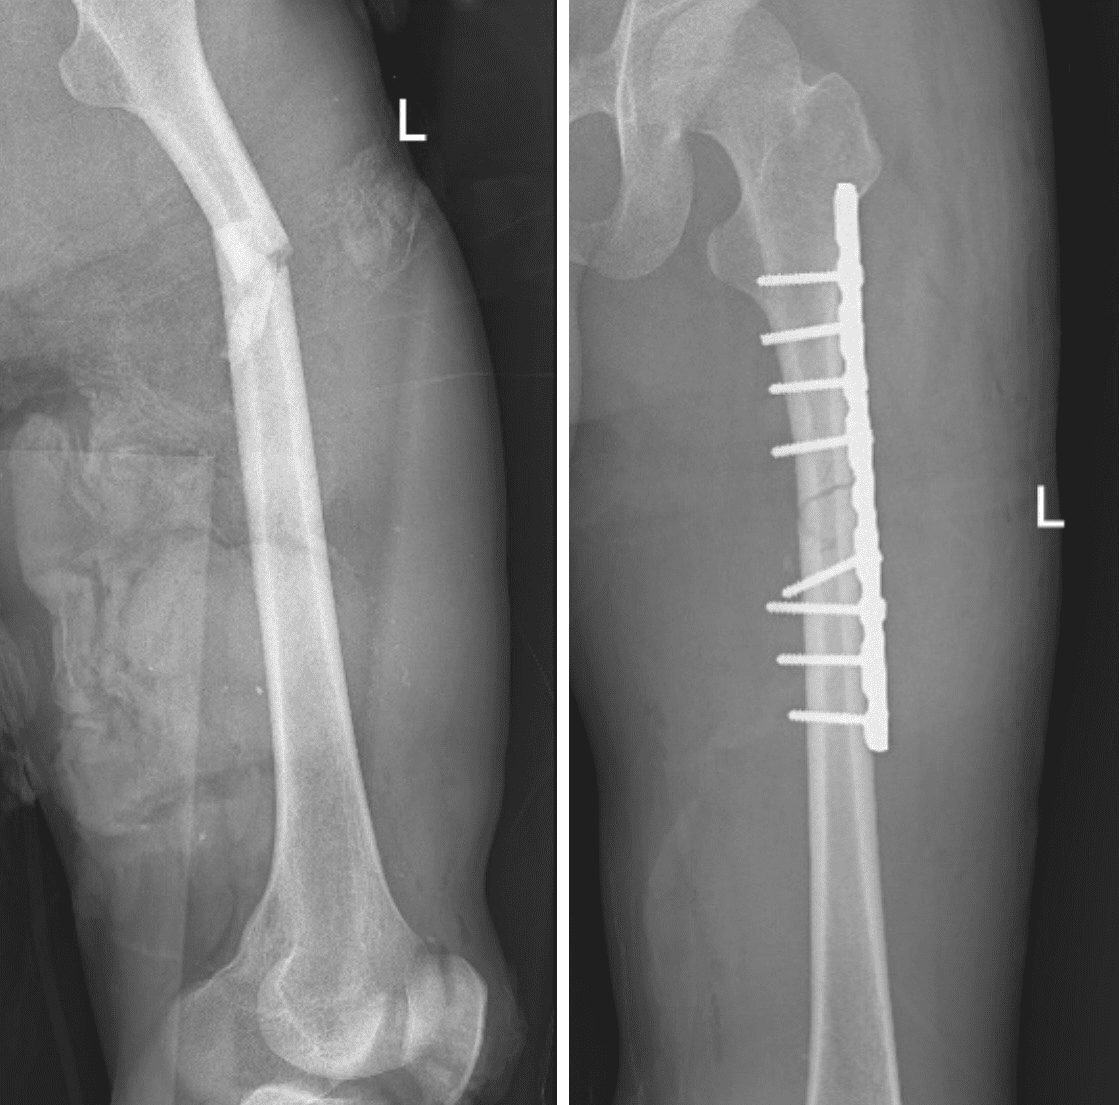

Hình ảnh chụp X-Quang trước và sau khi phẫu thuật

Đêm ngày 29/10/2023, Trung tâm y tế thành phố Móng Cái tiếp nhận bệnh nhân Hoàng V. T (28 tuổi, trú tại Bình Lộc – Lạng Sơn) bị tai nạn giao thông, nhập viện trong tình trạng sốc mất máu do đa chấn thương - Gãy hở độ 3, 1/3 trên xương đùi trái, chấn thương vỡ khung chậu, chấn thương bụng kín- vỡ ruột non.

Ekip phẫu thuật bác sĩ chuyên khoa Ngoại, Gây mê – hồi sức đã tiến hành phẫu thuật kết hợp xương đùi trái bằng nẹp vít, mở ổ bụng khâu lỗ thủng ruột non. Bệnh nhân được hồi sức tích cực, truyền máu, chống sốc trong suốt quá trình phẫu thuật.